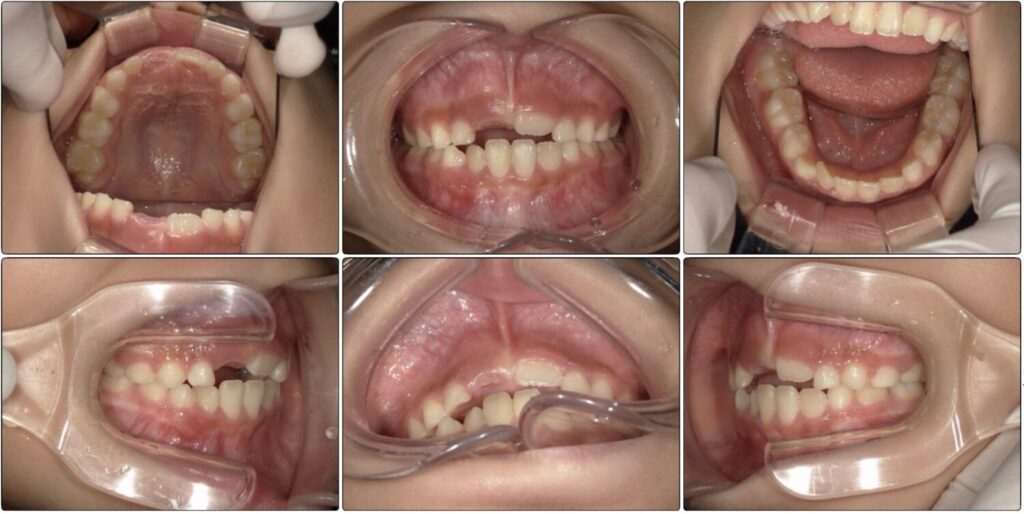

治療前 / 現在

治療開始時

初めにこの女の子はそこまで歯並びは悪くないのかもしれません。

下の歯にがたつきはあるのですが今の生え変わりだけでは片方の前歯も出ていないためパッと見た時に歯並び、悪いかな?くらいになることも多いと思います。